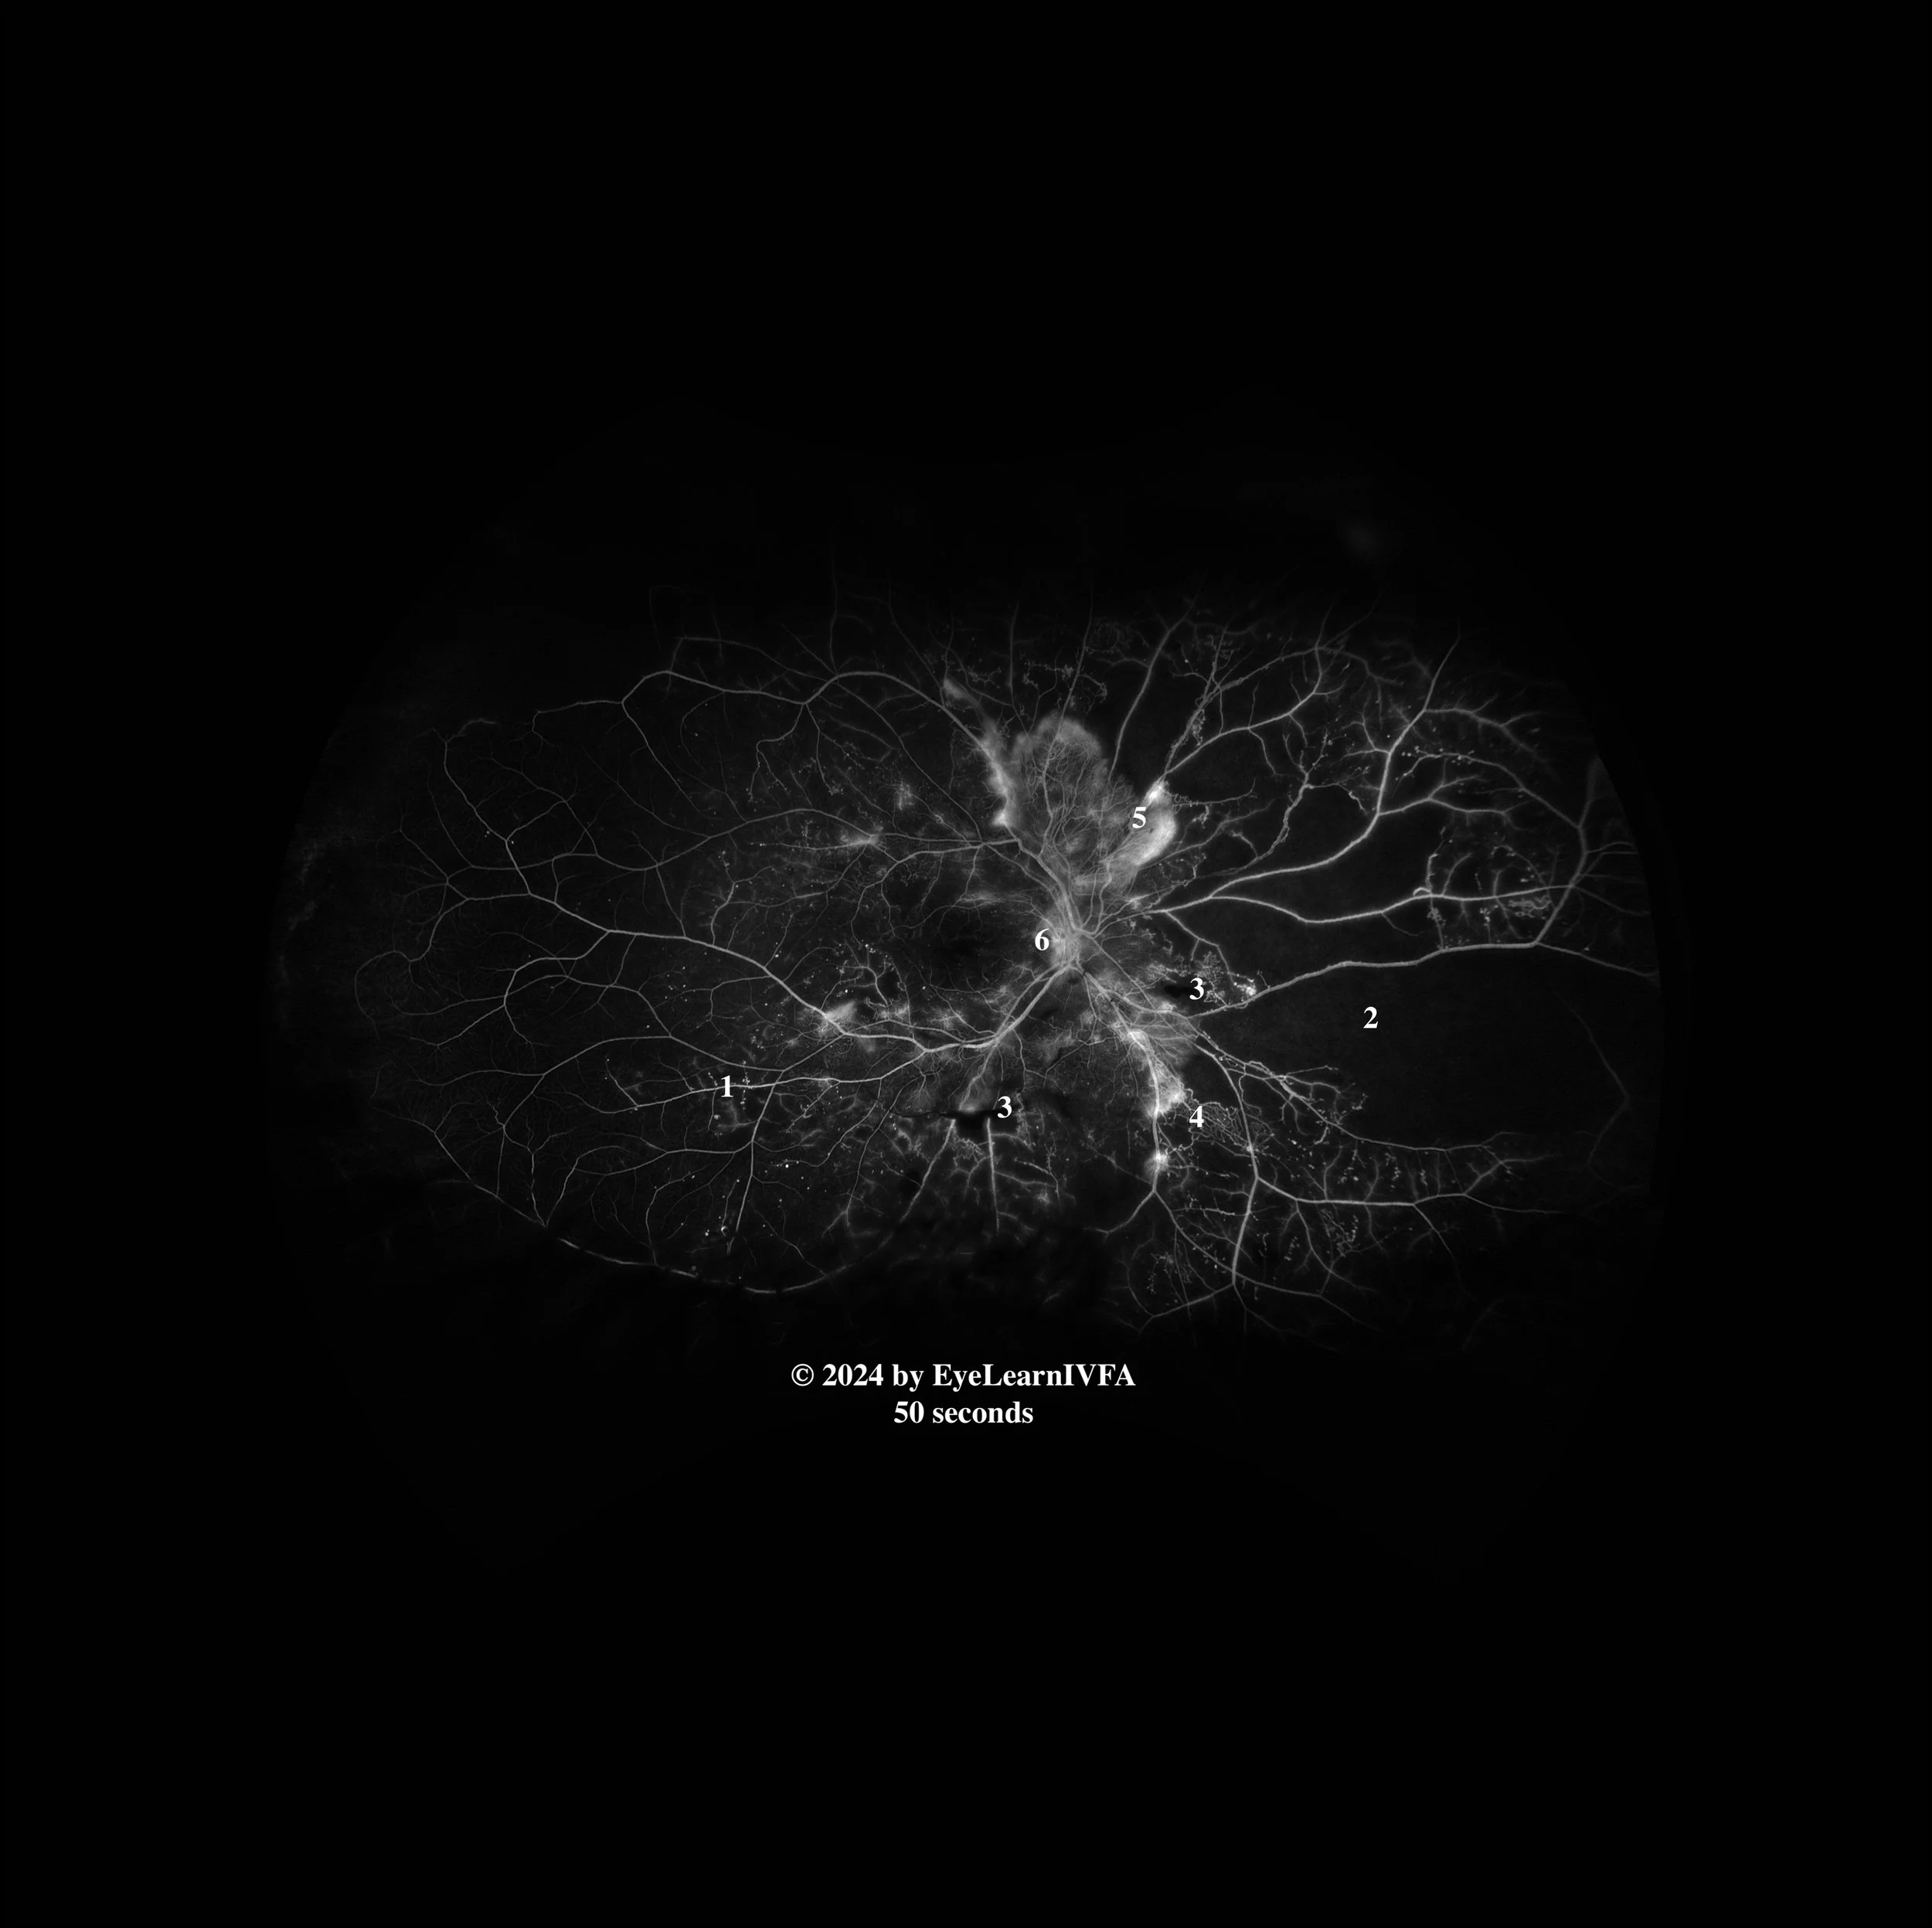

• IVFAs at 50 seconds

Late Arteriovenous Phase

Key Features:

• Persistent findings from previous images. This includes microaneurysms (1), IRMAs (4) and more distinct capillary non-perfusion (2).

• Regions of blocked fluorescence from pre-retinal/vitreous hemorrhage persist with stable appearance (3).

• Increased intensity of hyperfluorescence with indistinct borders at disc and periphery secondary to NVD (6) and NVE (5).